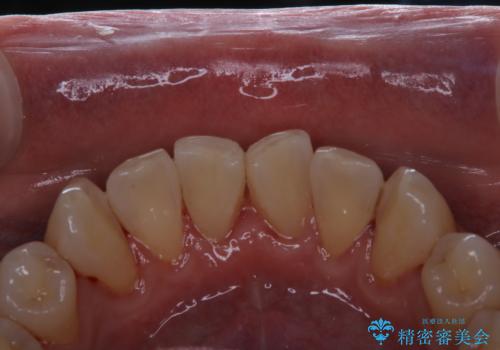

- 40年ほど歯科医院へ行ってなく、ザラつきがきになるとの事で来院されました。最近は普段の歯磨きの際、出血することがあり、歯ブラシ指導も希望されました。

お口全体に、歯垢・歯石が付着していたため、自費クリーニング(PMTC)60分コースを行い、徹底的に除去しました。

終了時

40年ぶりの来院との事で全体的に、古くからの歯垢・歯石が硬く多く付着していたため、自費クリーニング(PMTC)60分1万円+TAXコースを行いました。

よって、歯科衛生士による専門的なクリーニングを定期的に行うことがとても大切です。